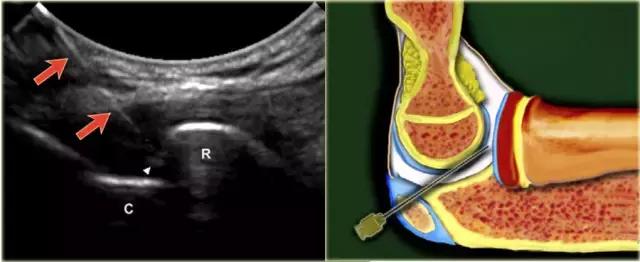

对于肘的注射,患者仰卧,臂在90°弯曲,升高并搁置在垫子上。桡骨小头与肱骨小头之间的关节间隙很容易触及。 手必须是旋前或可以变成拇指向上的位置,以最大程度地打开关节。

探头被放置在关节可视关节间隙。针(22号,30mm)在关节的背外侧朝向朝向桡骨头的关节表面的关节空间以微小的头尾向角指向。

当看到已经进入关节并且感觉到径向头部的软骨时,针被稍微拉回,以确保斜面从离开软骨并且面向关节。注射5-8mL的造影剂。 不应感觉到注射阻力。